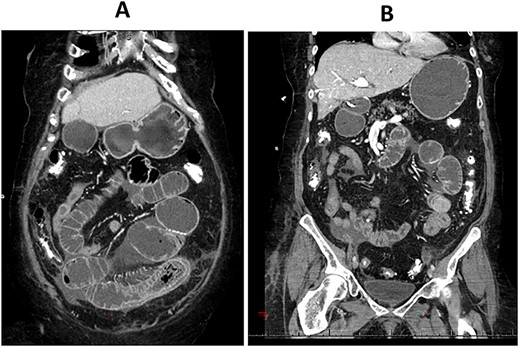

CT enterography: coronal views demonstrating dilatation of the bowel loops in the left lower quadrant associated with bowel thickening and collapsed small bowel loops distally.

The patient is a 71-year-old white female with a past medical history of PSC who underwent orthotopic deceased donor liver transplant in 2006 with a Roux-en-Y hepaticojejunostomy biliary anastomosis. Cholecystectomy was performed to the donor liver. Her course has been complicated over the years by recurrent cholangitis requiring a permanent percutaneous biliary drainage tube. The patient had a liver biopsy in 2011 which showed recurrent PSC, but the patient refused any further liver transplants. Her daily immunosuppressive regimen consisted of cyclosporine 25 mg. Thirteen years after the deceased donor liver transplant, the patient presented to our emergency department with abdominal pain for a week which was associated with abdominal distention and nausea. Her liver function tests and complete blood count were normal on admission. Computed tomography (CT) scan of her abdomen and pelvis with intravenous contrast demonstrated focal dilatation of proximal jejunal bowel loop at the site of anastomosis with air-fluid/debris level (Supplementary Figure 1). She was admitted to the hospital and was initially managed conservatively with nasogastric tube suction, bowel rest and intravenous fluid hydration. A small-bowel follow-through study was obtained which revealed contrast within the colon with no radiographic evidence of bowel obstruction. The patient’s clinical condition improved on her second day after admission and a trial of diet was performed, but the patient had worsening symptoms and subsequently developed peritonitis on her fourth hospital day. CT enterography was obtained which revealed dilatation of the proximal small bowel loops proximal to the small bowel anastomosis in the left mid-abdomen with mild wall thickening of the small bowel in the left lower quadrant without definitive obstructing cause or evidence of pneumatosis (Figs 1A–C and 2A,B). The patient was taken emergently to the operating room for an exploratory laparotomy. The jejunojejunostomy was intact and dilated with dilated proximal Roux limb. Approximately, 50 cm distal to the jejunojejunostomy in the common limb, a firm, round mass was palpated in a segment of bowel which was very edematous, friable, inflamed, with a focus of necrosis without obvious perforation. The remainder of the small bowel was normal. Given the state of the small bowel with the focus of necrosis, the decision was made to perform a small bowel resection with a hand-sewn anastomosis. The resected small bowel was opened off the field, and an impacted bezoar was found with small circular yellowish objects thought to possibly be gallstones mixed with other fibrous content. The resected small bowel pathology showed focal mucosal ulceration, transmural hemorrhage and acute serositis. The patient had an uneventful post-operative course and was discharged home 7 days after surgery. She was seen in clinic for a follow-up appointment a month after the surgery and was found to be doing great, tolerating her diet and having regular bowel function.